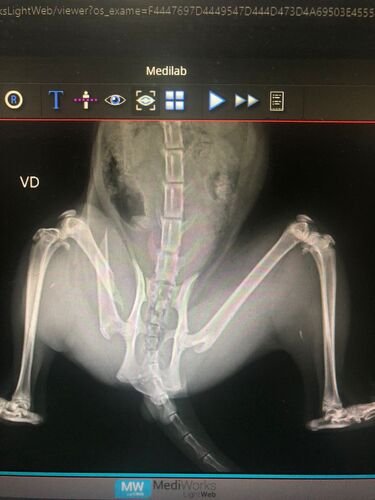

Sou Laura e criei essa vaquinha no intuito de poder realizar a cirurgia de fêmur do Cookie, um gatinho que foi atacado por um pitbull, precisamos realizar a cirurgia o mais rápido possível, pois o animalzinho está com muitas dores e estamos fazendo o possível e o impossível para salva-lo! A cirurgia será feita pelo hospital popular veterinário da prefeitura e esperamos ter êxito. Por favor nos ajude a salvar a vida do Cookie.